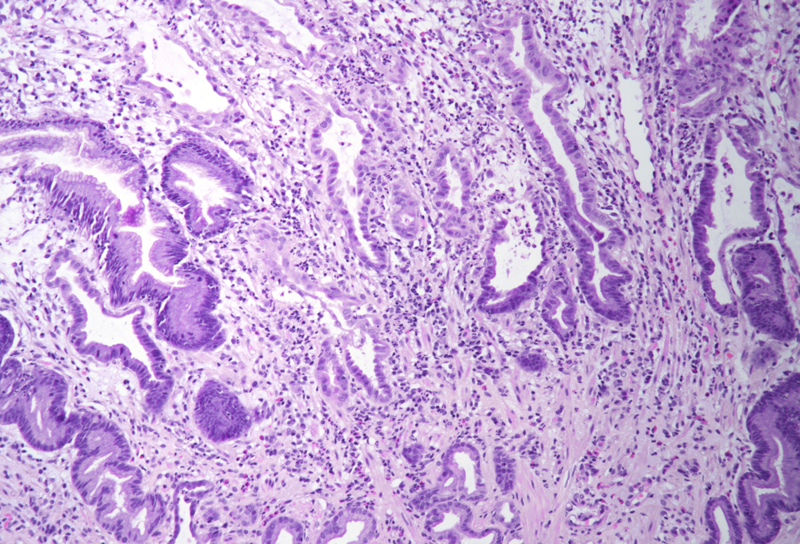

Histology showed an extremely altered gastric mucosa, with architectural distortion by glandular atrophy, degenerative epithelial changes, erosions and an expanded oedematous lamina propria (PANEL A-C). On higher magnification, the lamina propria contained a mixed inflammatory infiltrate, characterized by lymphocytes, plasma cells, eosinophils and neutrophils, focally with abscess formation. We observed withering glands lined by flattened eosinophilic epithelium, occasionally containing apoptotic debris (PANEL D-E); in other areas, little atrophic neuroendocrine nests were found (PANEL F). In summary, there was a severe acute inflammation and signs of acute epithelial injury highly suggestive of a drug-induced gastritis, consistent with injury due to pembrolizumab.